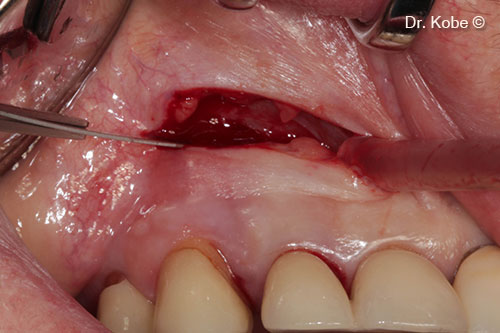

Horizontal incision (NIPSA) in the vestibule